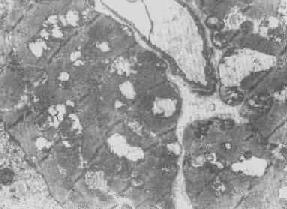

心肌细胞线粒体

图1-8 心肌细胞线粒体

线粒体为线状、长杆状、卵圆形或圆形小体,外被双层界膜。外界膜平滑,内界膜则折成长短不等的嵴并附有基粒。内外界膜之间为线粒体的外室,与嵴内隙相连,内界膜内侧为内室(基质室)(图1-8)。在合成甾类激素的内分泌细胞(如肾上腺皮质细胞、卵甾滤泡细胞、睾丸的Leydig细胞等),线粒体嵴呈小管状。内外界膜的通透性不同,外界膜的通透性高,可容许多种物质通过,而内界膜则构成明显的通透屏障,使一些物质如蔗糖和NADH全然不能通过,而其他物质如Na+ 和Ca 2+等也只有借助于主动运输才能通过。线粒体的基质含有电子致密的无结构颗粒(基质颗粒),与二价阳离子如Ca2+及Mg2+具有高度亲和力。基质中进行着β氧化、氧化脱羧、枸橼酸循环以及尿素循环等过程。在线粒体的外界膜内含有单胺氧化酶以及糖和脂质代谢的各种转移酶;在内界膜上则为呼吸链和氧化磷酸化的酶类。